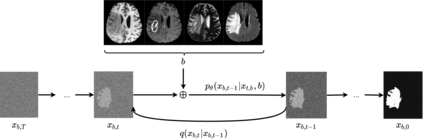

Diffusion models have shown impressive performance for generative modelling of images. In this paper, we present a novel semantic segmentation method based on diffusion models. By modifying the training and sampling scheme, we show that diffusion models can perform lesion segmentation of medical images. To generate an image specific segmentation, we train the model on the ground truth segmentation, and use the image as a prior during training and in every step during the sampling process. With the given stochastic sampling process, we can generate a distribution of segmentation masks. This property allows us to compute pixel-wise uncertainty maps of the segmentation, and allows an implicit ensemble of segmentations that increases the segmentation performance. We evaluate our method on the BRATS2020 dataset for brain tumor segmentation. Compared to state-of-the-art segmentation models, our approach yields good segmentation results and, additionally, detailed uncertainty maps.